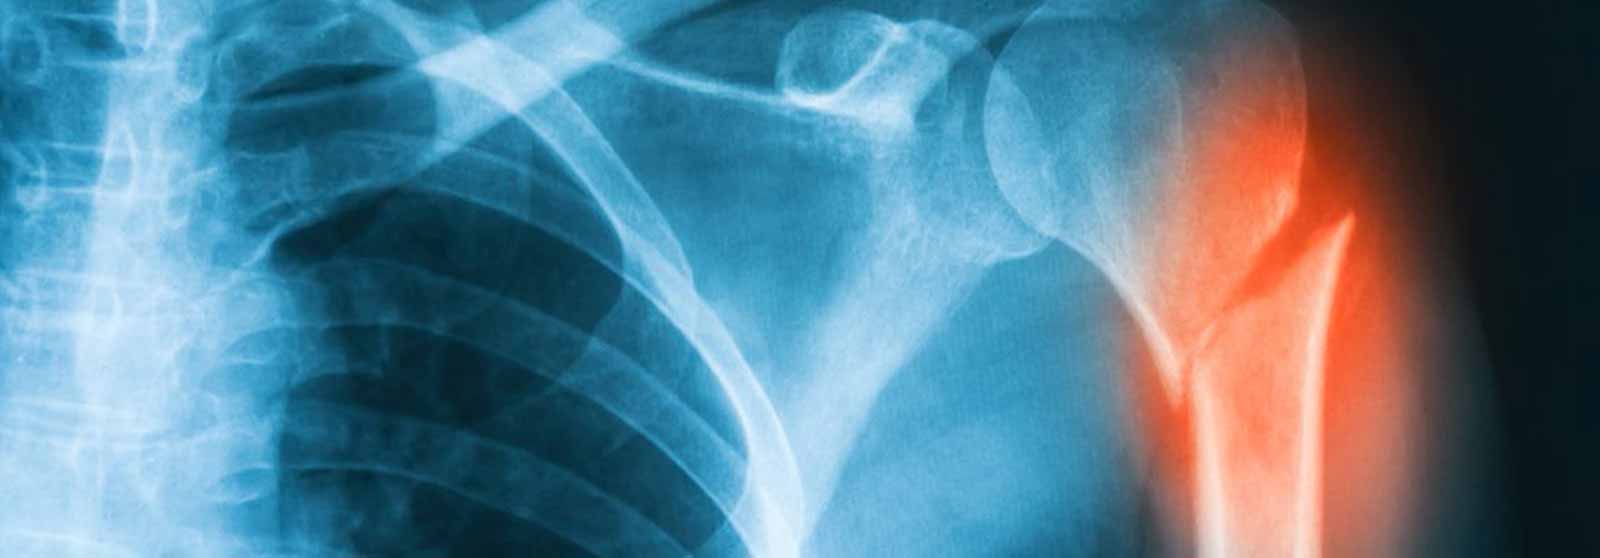

X-ray image of shoulder AP view